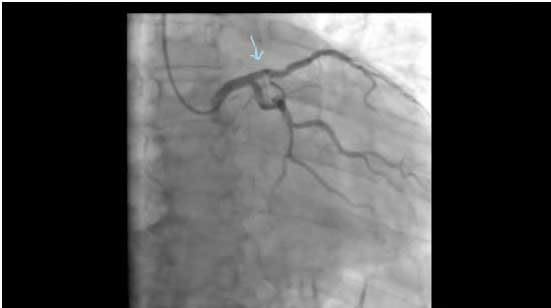

με την τεχνική της περιστροφικής αθηρεκτομής (rotablation). Αρχικά η στένωση προσπελάστηκε από σύρμα οδηγό μέσω του οποίου

προωθήθηκε μέχρι το επίπεδο της βλάβης ο αθηροτόμος (rotablator). Μετά την επιτυχή διάνοιξη τοποθετήθηκε ενδοαρτηριακή πρόθεση (σχήμα

3).